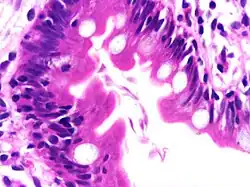

Giardióza je parazitární průjmové onemocnění střevního traktu zvířat a člověka způsobené bičíkovcem Giardia intestinalis. Onemocnění se projevuje hlenovitým, i krvavým průjmem s velkým obsahem tuků – steatorea. Klinické příznaky jsou výraznější u mladých jedinců, u dospělých většinou latentní průběh. Postižený jedinec hubne, trpí nechutenstvím. Jedná se o zoonózu a řadí se mezi oportunní infekce. Onemocnění se potvrzuje nálezem cyst mikroskopickými technikami – je zapotřebí několikrát zopakovat vyšetření, protože cysty jsou vylučovány nepravidelně. Léčí se 5-nitroimidazoly, pro terapii zvířat nejčastěji používán metronidazol. Při nakažení domácích zvířat (kočky, psa, králíků, hlodavců – nejčastěji činčil) je nutné přeléčit všechna zvířata a člověk se musí chránit dodržováním hygienických zásad.